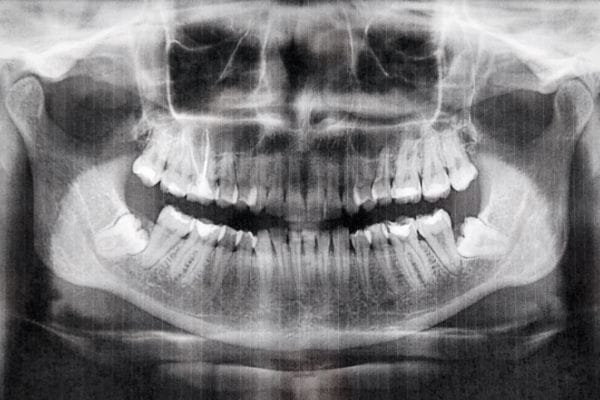

2. Radiografías: panorámica y telerradiografía

Una vez realizado el estudio clínico, se toman radiografías, como la panorámica y la telerradiografía. Estas imágenes permiten al especialista visualizar los huesos y las raíces de los dientes, lo que ayuda a identificar problemas que no se ven a simple vista. Las radiografías son esenciales para determinar la mejor estrategia de corrección.